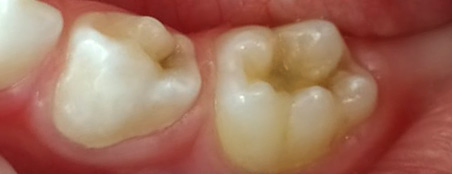

Эстетические реставрации. Дошколятам нравятся цветные пломбы, а детям постарше врач поставит пломбу, точь-в-точь совпадающую по цвету, форме и рельефу с натуральным зубом.

Зачаток постоянного зуба расположен прямо под корнями молочного. Если в молочном зубе инфекция, она часто переходит на постоянный зуб. В результате тот прорезывается уже нездоровым или не вырастает совсем.

В зубах с нелечеными кариозными полостями обитают стафилококки и стрептококки. Постоянный очаг инфекции снижает иммунитет ребенка, повышает риск ОРЗ и болезней внутренних органов.

Дети, и особенно подростки, остро реагируют на недостатки во внешности. Если не хватает нескольких зубов, некоторые черные из-за устаревшей технологии серебрения, а постоянные растут неровными — это может стать для ребенка испытанием.